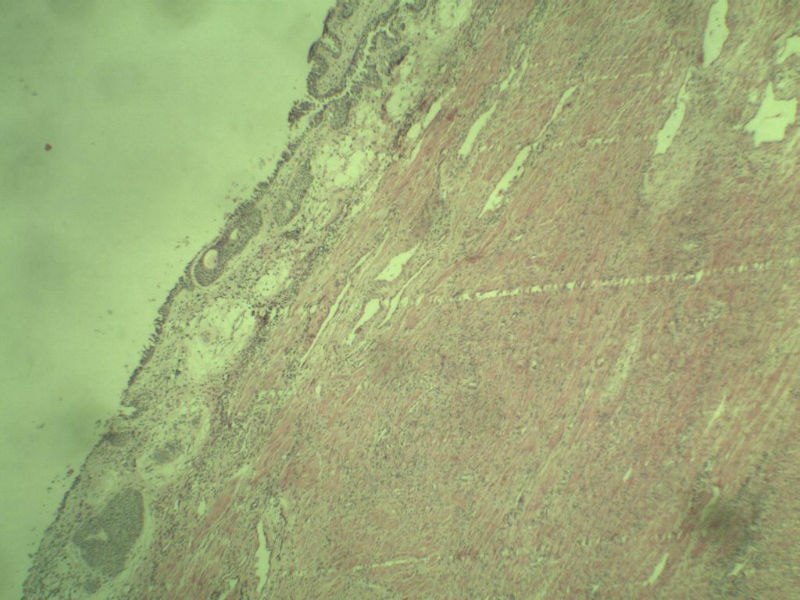

男 75岁 因排尿困难半年行前列腺切除术,体积 4 × 3 × 2.5 cm3,切面灰白,实性,质韧。请各位老师看看 有问题没? 谢谢了!

前列腺增生症伴鳞化

良性前列腺增生

良性前列腺增生伴尿路上皮化生

前列腺增生,有腺瘤样结节形成。

前列腺增生伴尿路上皮鳞化及Brown巢形成,未见恶性。

前列腺结节性增生